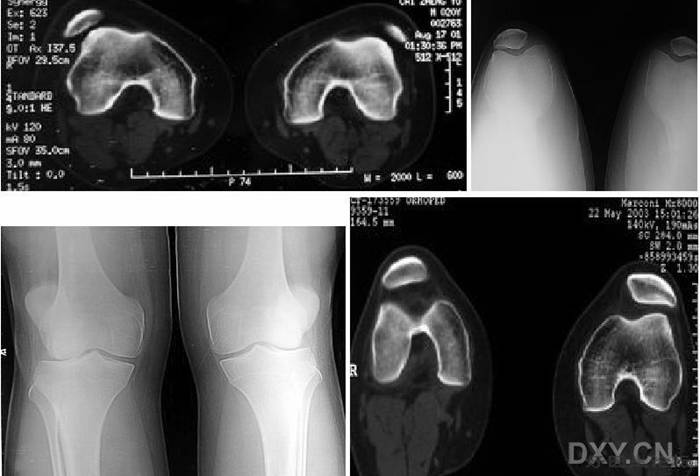

分裂 (二分)髌骨 Bipartite Patella

* 常见于儿童,多双侧性

* 一般认为是正常骨化的变异,可在十几岁时融合

* 症状:

– 运动时疼痛或运动后疼痛

– 膝关节屈曲时疼痛、下跪时疼痛

– 上下楼梯时疼痛

– 行走时疼痛

– 受冷时疼痛

– 无症状

* 体征:

– 分裂部扣击痛:可诱发有症状的分裂髌骨的疼痛,无症状者阴性

– 分裂骨片局部骨性隆起

– 股四头肌萎缩

– 髌骨摩擦音

– 大多无关节积液、跛行和关节活动度受限

l  有时需与骨折鉴别

11.jpg

12.jpg